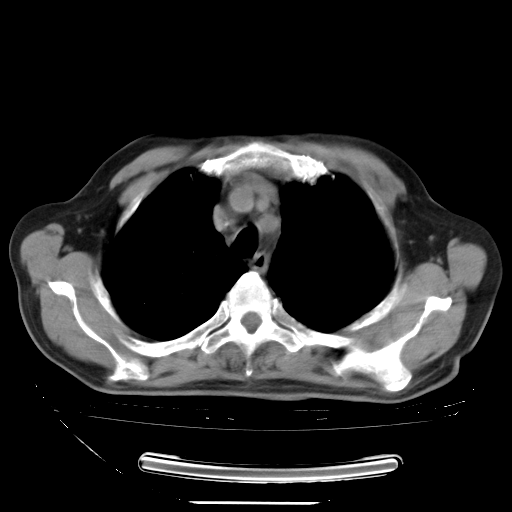

今天复查肺部CT,发现双肺广泛磨玻璃样改变。所以我把3月19日和5月9日相隔50天的肺部CT上传。请大家会诊。

2009年3月19日肺部CT片。

2009年3月19日肺部CT

大致读了系列胸部CT:纵隔窗无明显异常,肺窗:从4、27至今:主要是双肺中下野外带可见毛玻璃样改变,目前处于急性肺泡炎阶段,至于原因考虑1、结替组织或胶原血管性疾病所致?2、恶性疾病如恶组在肺部所致的表现或细支气管肺泡癌?3、药物或其它原因如肺蛋白沉着症所致肺泡炎目前不太可能?总之,明天就去请我院的呼吸科、感染科、血液科和临免专家会诊哈。